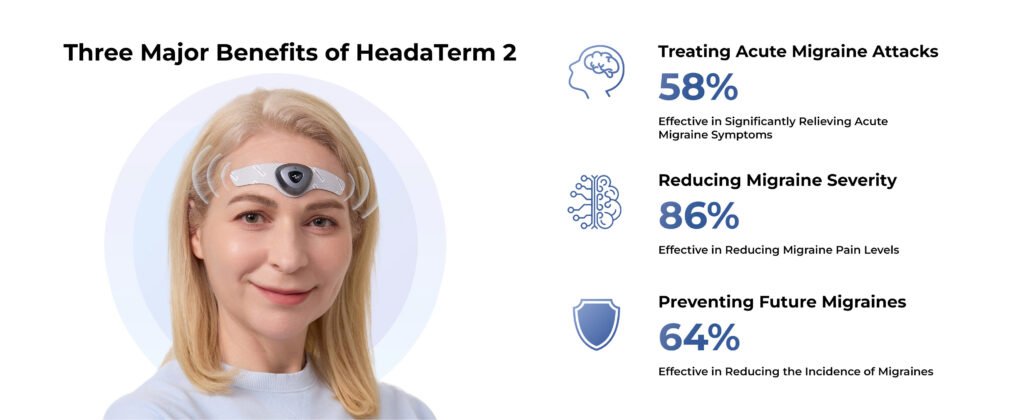

HeadaTerm 2 is a clinically proven, safe, and effective medical device worn on users’ foreheads that uses none-invasive neuronal electrical stimulation technology to prevent and treat primary headache, including migraine, tension headache, cluster headache.

HeadaTerm is FDA cleared. It is a product specifically designed to target and alleviate migraines, using a more precise eTNS(external trigeminal nerve stimulation) technology. It can only be worn on the forehead area.